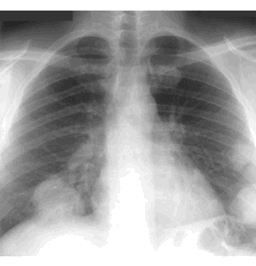

CASE 2

How would you describe the LUNG abnormality in each of these cases?

B

hint: this one is hard to see...